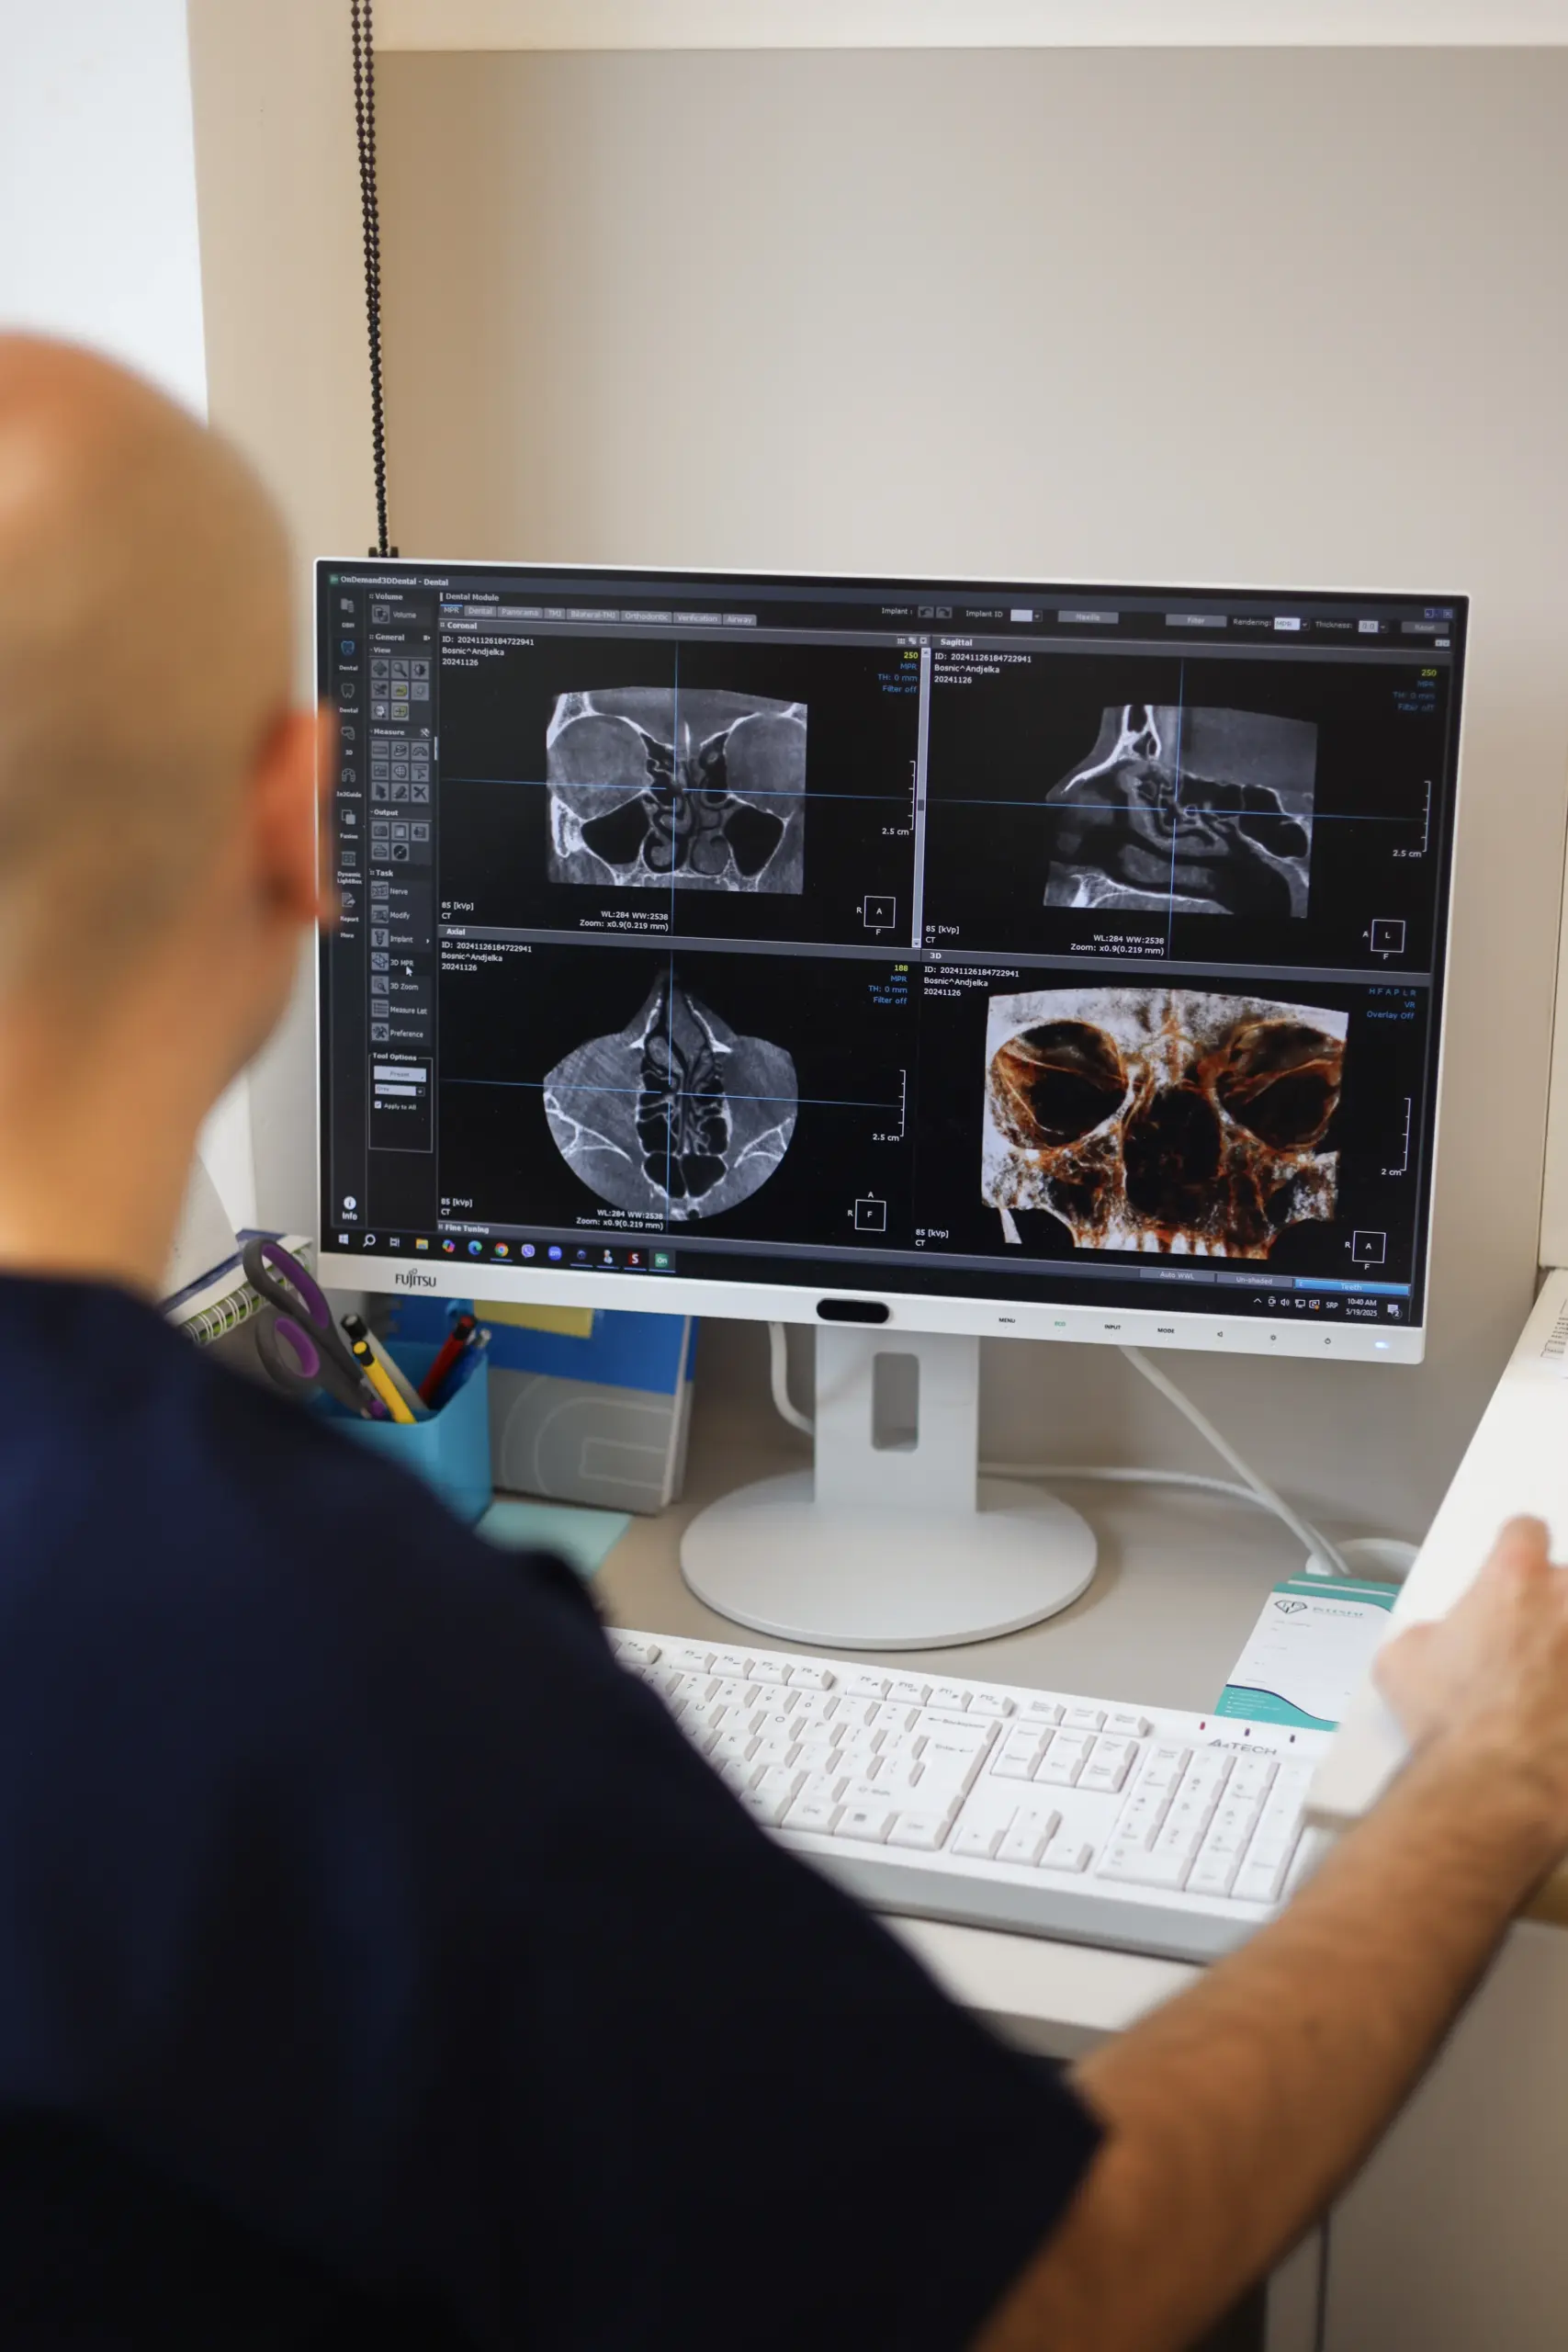

Imaging 2D-3D dei denti